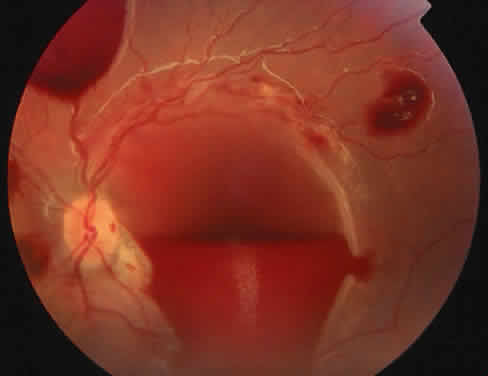

The most common ocular manifestations of TTP include papilledema, extraocular muscle palsies, and visual field defects, which usually are secondary to concomitant CNS involvement.75 Retinal findings consist of hemorrhages, retinal vascular occlusions, and serous detachments76,77 (Figs. 8 to 10). The cause of the serous detachments appears to be focal occlusion of the choriocapillaris resulting in retinal pigment epithelial damage and blood-retinal barrier disruption.76,77 Findings on fluorescein angiography are characterized by focal areas of nonperfusion of the choriocapillaris associated with late leakage into the subretinal space76 (Fig. 11). This is consistent with histopathologic studies that show occlusion of the choriocapillaris and large choroidal vessels, presumably by fibrin, with overlying necrosis of thepigment epithelium.75,76 TTP also has been linked in one case report with Purtscher retinopathy.78

Fig. 11. Fluorescein angiogram of patient with thrombotic thrombocyto-penic purpura showing late choroidalhyperfluorescence caused by focal areas of choriocapillaris nonperfusion. (Courtesy of Jerry Neuwirth, MD.)

Clinically, the development of serous retinal detachments usually is associated with exacerbations of TTP and the development of acute hypertension. Although serous retinal detachments have been described as a preterminal event, resolution of the detachments with subsequent pigment epithelial changes may occur when the underlying hypertension and thrombocytopenia are controlled.77